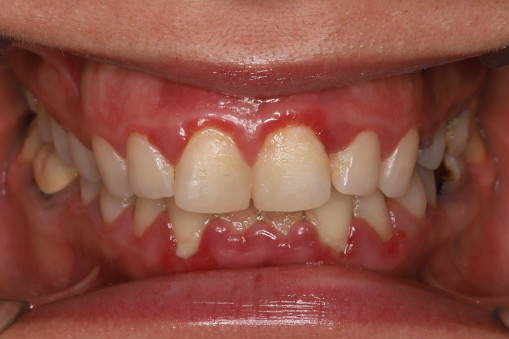

А прежде, чем вы посмотрите фотографии «до» и «после» лечения слизистой оболочки полости рта, проведенных в нашей клинике, хочу поблагодарить большое количество наших пациентов, которые поверили, прониклись нашей концепцией, и мы вместе, именно вместе победили болезни десны, гингивит и пародонтит!

До/после лечения